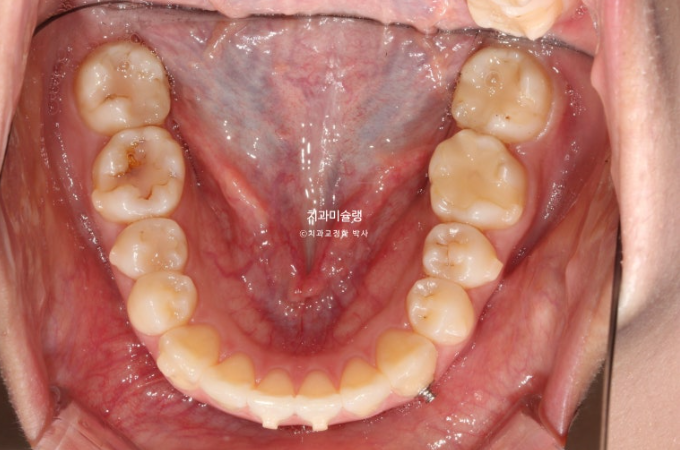

25.03~25.12

이 사진에서 보듯 치아가 초진에 비해 작아질 정도까지 치간삭제를 하지는 않습니다.

만약 치아가 작아보일 정도까지 했거나 치아가 시려질때 까지 했다면 그건 치간삭제를 너무 과하게 한거죠.

통상 에나멜층에 한정해서 부위당 0.2mm씩 최소량 시행하면 치료에 도움이 됩니다.

그러나 그 양이 과하면 치아건강을 해지게 되겠죠.

과유불급 이라는 말처럼요.